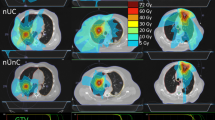

A total of 15 lung cancer patients previously treated with 3D or VMAT SBRT were randomly selected. For each patient, non-coplanar 3D, coplanar and non-coplanar VMAT and flattening filter free VMAT (FFF-VMAT) plans were generated to meet the same objectives with 50 Gy covering 95% of the PTV. Two dynamic arcs were used in each VMAT plan. The couch was set at ± 5° to the 0° straight position for the two non-coplanar arcs. Pinnacle version 9.0 (Philips Radiation Oncology, Fitchburg WI) treatment planning system with VMAT capabilities was used. We analyzed the conformity index (CI), which is the ratio of the total volume receiving at least the prescription dose to the target volume receiving at least the prescription dose; the conformity number (CN) which is the ratio of the target coverage to CI; and the gradient index (GI) which is the ratio of the volume of 50% of the prescription isodose to the volume of the prescription isodose; as well as the V20, V5, and mean lung dose (MLD). Paired non-parametric analysis of variance tests with post-tests were performed to examine the statistical significance of the differences of the dosimetric indices.

Dosimetric indices CI, CN and MLD all show statistically significant improvement for all studied VMAT techniques compared with 3D plans (p < 0.05). V5 and V20 show statistically significant improvement for the FFF-VMAT plans compared with 3D (p < 0.001). GI is improved for the FFF-VMAT and the non-coplanar VMAT plans (p < 0.01 and p < 0.05 respectively) while the coplanar VMAT plans do not show significant difference compared to 3D plans. Dose to the target is typically more homogeneous in FFF-VMAT plans. FFF-VMAT plans require more monitor units than 3D or non-coplanar VMAT ones.

Table 1 lists the statistical data of the dosimetric indices for all the studied cases. Overall, VMAT plans demonstrate better indices than the 3D plans. The non-coplanar VMAT plans yield slightly better indices than the coplanar ones. The GI values for the FFF-VMAT plans were slightly lower than those for conventional plans. VMAT required higher total MUs than 3D. The FFF-VMAT plans tended to use the highest number of MU.

Due to the large differences in PTV size as well as individual patient anatomical variations, the standard deviations in Table 1 are quite high. This large spread somewhat obscures the dosimetric differences between the plans. To better illuminate the differences, all the plans were compared with the corresponding 3D plans taken as a reference. The numbers of cases out of the 15 cases studied that dosimetrically favor the VMAT or FFF-VMAT plans are presented in Table 2. Except for the total MUs, more cases favor the VMAT and FFF-VMAT plans for all other dosimetric indices.

Conformity index (CI)

The overall Friedman test demonstrated highly significant difference between the techniques (p < 0.0001) for the CI. Individual comparisons (Dunn's post-test) for the CI indicate statistically significant difference between the 3D and all VMAT techniques: p < 0.05 between the 3D and the coplanar VMAT plans, p < 0.01 between 3D and the non-coplanar VMAT plans and p < 0.001 between 3D and the FFF-VMAT plans,. The differences were not significant (p > 0.05) between different VMAT plans. VMAT offers statistically significant improvement in CI over 3D.

Conformity number (CN)

Similar to CI, the Friedman test indicated overall significant difference in CN (p < 0.0001). The p values of the Dunn's post-test were p < 0.05 between 3D and the coplanar VMAT plans, p < 0.01 between 3D and the non-coplanar VMAT plans and p < 0.001 between 3D and the FFF-VMAT plans. No significant difference in CN between VMAT techniques could be established (p > 0.05)

Gradient index (GI)

The overall p value from the Friedman test was 0.0035 for GI. The Dunn's test yielded p < 0.05 between 3D and the non-coplanar VMAT plans and p < 0.01 between 3D and the FFF-VMAT plans. The test demonstrated no significant GI improvement (p > 0.05) for coplanar VMAT compared to 3D, and no significant differences among the different VMAT techniques.

V20, V5 and mean lung dose (MLD)

From the overall Friedman test, p < 0.0001 for V20. A statistically significant improvement in V20 was found for non-coplanar VMAT (p < 0.01) and FFF-VMAT (p < 0.001) techniques compared to 3D. No significant difference in V20 was found between 3D and coplanar VMAT, as well as between different VMAT techniques.

The Friedman test yielded p = 0.0002 for V5 comparisons. Individual comparisons showed no statistically significant differences, except for the FFF-VMAT plans indicating improvement in V5 compared to 3D (p < 0.001).

The Friedman test was significant (p < 0.0001) for MLD comparisons. The Dunn's post test demonstrated that all VMAT techniques showed improvement in MLD compared to 3D with p < 0.05 between 3D and the coplanar VMAT, p < 0.01 between 3D and the non-coplanar VMAT and p < 0.001 between 3D and FFF-VMAT. No significant difference in MLD was shown between the VMAT techniques. The gEUDs for the normal lung closely followed the MLD.

The VMAT advantage in shortening the treatment time compared to 3D non-coplanar plans is well known [9]. The current study also shows that VMAT plans are more likely to give statistically better target conformity and sharper dose fall-off in normal tissues. The average GI value for FFF-VMAT plans was lower than that for 3D plans, indicating better dose fall-off in normal tissues in the FFF-VMAT plans. At the same time, V20 and V5 were lower when treating with FFF-VMAT. V20 was also lower in non-coplanar VMAT plans than in 3D.